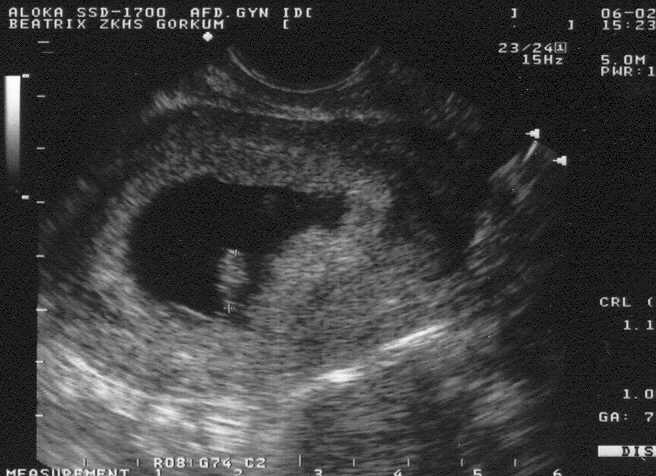

Hieronder s

taat de eerste's foto van haar. Door complicaties tijdens het begin van de zwangerschap moest er een aantal echo's gemaakt worden. Klik op de foto voor een vergroting.